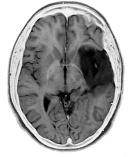

Walking and running can halve the chance of brain cancer

Running and walking reduce the likelihood of your developing a brain tumour. Walking for 36-72 minutes every day or jogging for 15-30 minutes gives optimal protection. Bio-statistician Paul Williams at Ernest Orlando Lawrence Berkeley National Laboratory discovered this after following 150,000 runners and walkers for over ten years.

In May 2014 Williams published the results of a study in Medicine & Science in Sports & Exercise, in which he examined the relationship between running, walking and brain cancer. Brain cancer is relatively rare, and scientists know little about the lifestyle factors that can protect against it.

The most common form of brain cancer is glioma. In-vitro studies have shown that IGF-1 stimulates the growth of glioma cells. Williams believes that physical exercise helps the muscles to absorb more IGF-1 from the blood, making less IGF-1 available for cancer cell growth.